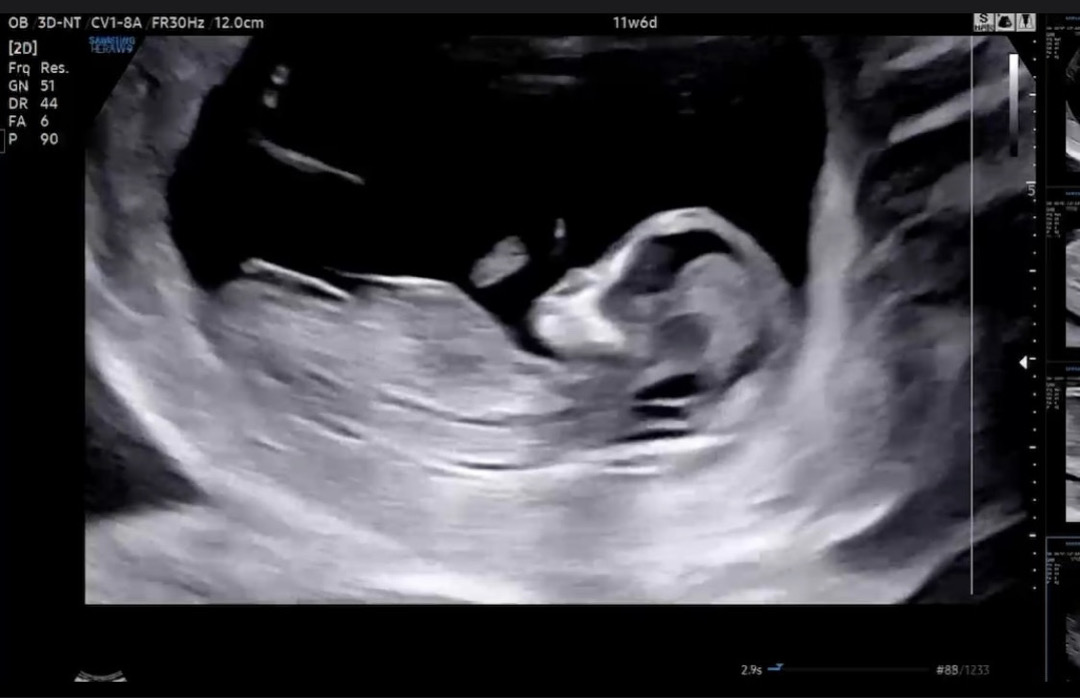

4주만에 만나고 왔어요🥹 목대 콧대 지극히 정상 수치받았지만, 혈액을 통해 한번더 체크해본다고 하더라구요😛 긴장해서 그런지 혈압도 그렇고 내리 잠만 잤네요😆 혹시 대강 느낌이 오나요? 딸인지 아들인지? 마구 의견주세요🫶

평행으로 보이는게 딸같아요..!